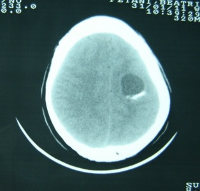

The poor woman was quite well until the night of 29th January 2011 when around midnight she started convulsing and was restless. Her husband wasted no time but rushed her to Malamulo SDA Hospital. She kept on having convulsions despite the treatment she was given. The clinicians worked her up and sent her for CT Scan of the brain (picture attached). That was at a place 60 kilometers away (37.2 miles). Lo and behold it was a tumor. So what next? The patient was referred to a larger hospital where nothing else was done.

If this patient had enough resources the tumor could have been removed at a private hospital and at a cost of about $1,000.00. Her husband cannot afford that.

Her condition is deteriorating day by day. Now the weakness on the right side of her body is worse than it was a month ago. If she were in the West, neurosurgeons would have booked her in to put their skills into use. Out here, we do not have a neurosurgeon. The local people will think any doctor can handle the case. Africa has challenges more than what is seen by a naked eye.